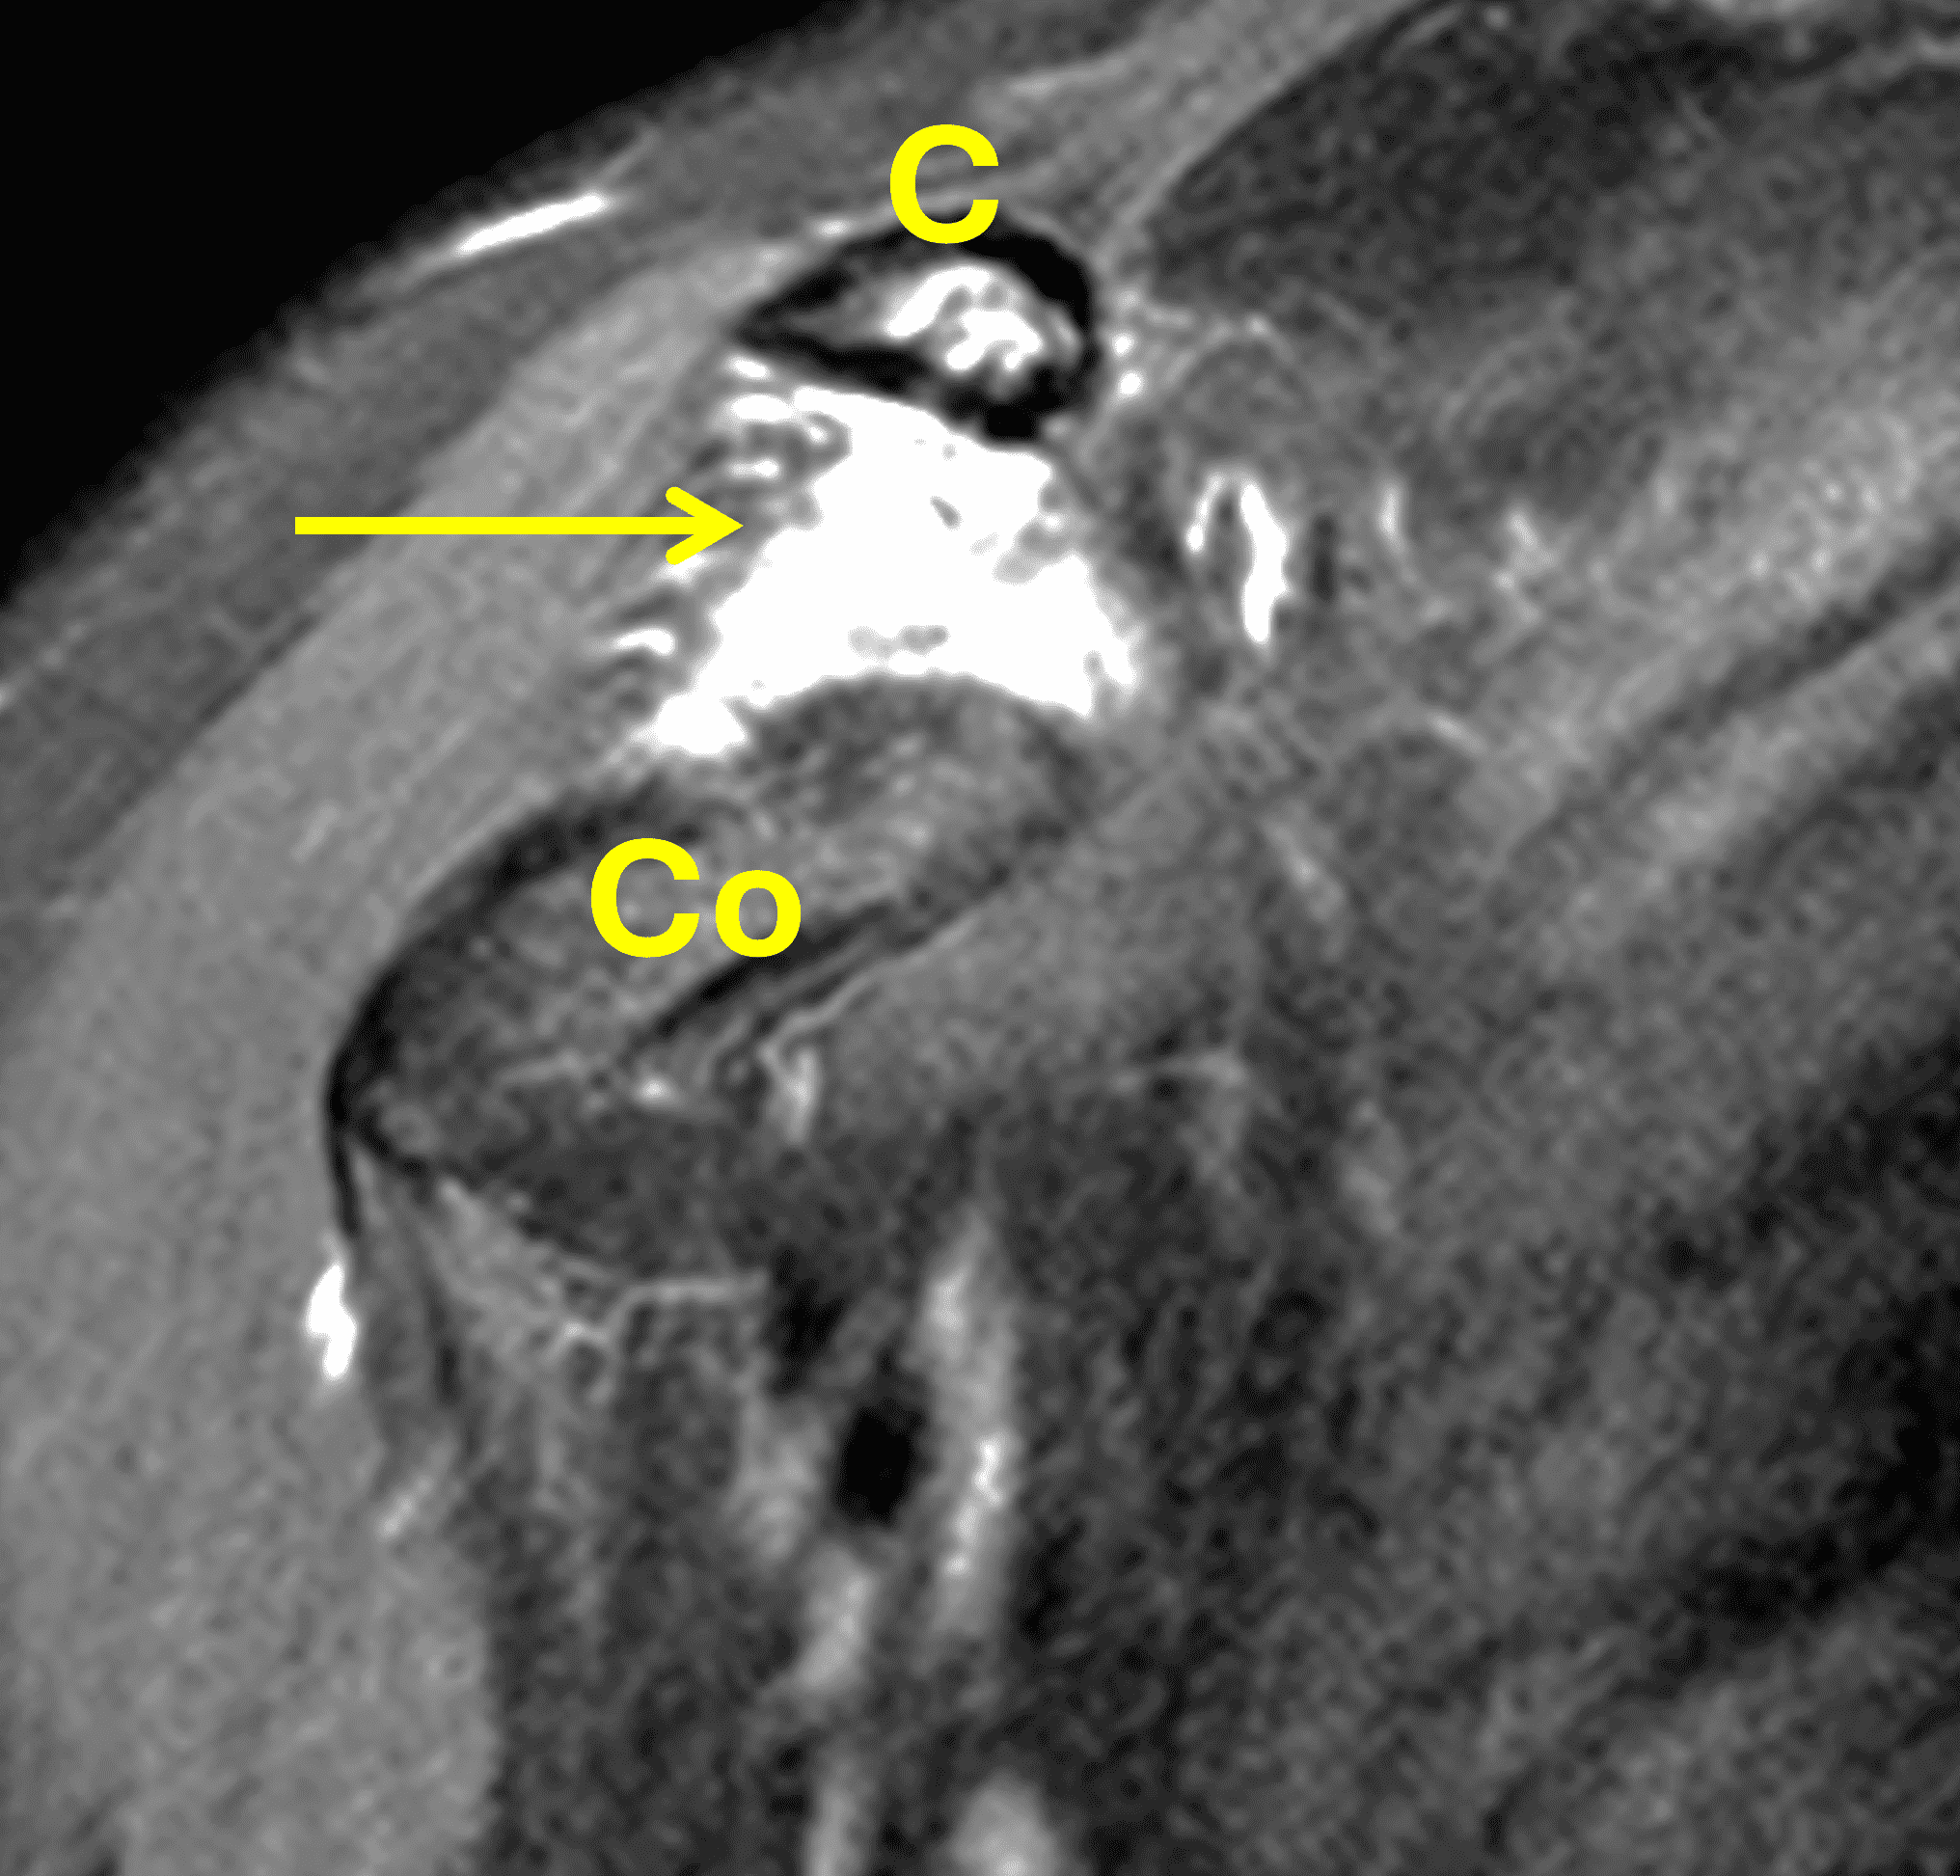

A 49-year-old male, avid weightlifter complains of chronic pain along the superior aspect of his right shoulder. He denies acute trauma. An AP radiograph (Figure 1A), as well as oblique coronal SPAIR (Figure 1B), axial fat-suppressed fluid sensitive (Figure 1C), and oblique sagittal T2-weighted images (Figure 1D) are shown. What are the findings? What is your diagnosis?

MRI: MRI is the primary imaging modality used for the diagnosis of DCO and identifies relevant findings earlier than radiographs or CT.  To differentiate DCO from similar conditions, it is important to identify underlying findings that are isolated to or more pronounced in the distal clavicle compared to other structures.  Osseous changes along both the acromial and distal clavicular margins of the joint often point to a different diagnosis.2

The principle MRI finding of DCO is distal clavicular marrow edema and surrounding inflammation on fluid-sensitive pulse sequences, especially with fat suppression (Figures 3 and 4).2, 9 Marrow changes can occur in patients with normal radiographs,10 in which case a term like “stress/overuse related marrow edema,” might be preferable to “osteolysis.” On MRI, more severe cases may show erosions or cysts in the distal clavicle and loss of the subchondral bone plate in addition to more pronounced marrow and soft tissue edema. A band of low signal paralleling the distal bone end may be present, suggesting a stress fracture line (Figure 5).8 However, a similar appearance can be due to the sclerotic rim surrounding distal clavicle cysts or small erosions (Figure 6). A small effusion or mild synovitis is often present in the AC joint.  Soft tissue edema within and surrounding the AC joint capsule and distal clavicular periosteum may be visible (Figure 3).  Some patients may also show marrow edema (or even erosions) in the anterior acromion, but the changes are typically more severe in the distal clavicle (Figures 5 and 7).2

While isolated DCO does not produce osteophytes, it may occur in patients with pre-existing osteoarthritis; in these cases, the marrow edema is typically out of proportion to the osteophytosis. When DCO occurs following an acute traumatic event like an AC joint separation, the MRI findings of that condition (e.g., widening or subluxation of the joint, disruption of the coracoclavicular ligaments) may be evident (Figure 8).1 Osteolysis can also develop following fractures of the distal clavicle, due to post-traumatic resorption of small, comminuted fracture fragments. In these cases, residual deformity of the clavicle or the presence of the original fracture lines may be evident on imaging studies. Additionally, because resorption of the fracture fragments typically occurs during the chronic healing after inflammation has resolved, marrow and soft tissue edema may not be present on MRI when the distal clavicular bone loss is seen.